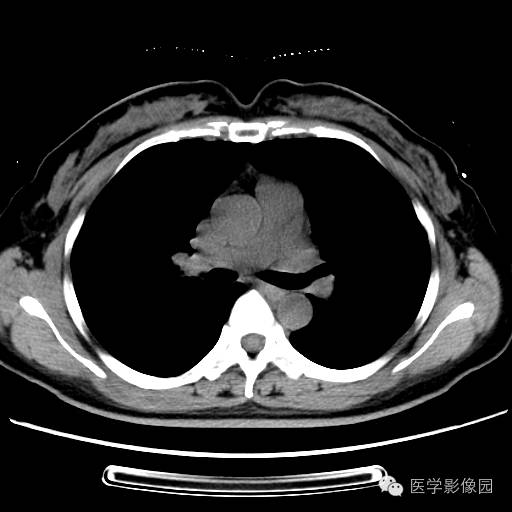

肺叶实变性支气管肺泡癌1例CT影像表现